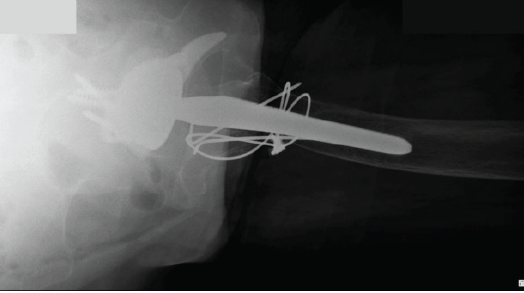

At 8 weeks postoperatively, the patient was pain-free, with a range of motion of 0–100° flexion, 30° abduction, 30° adduction, 30° internal rotation, and 30° external rotation. She had successfully resumed mobility, taking several steps with the assistance of a wheeled walker. At the 6-month follow-up, the patient reported walking and moving as she did before the trauma and surgery. Radiographic evaluation at that time confirmed implant stability and showed signs of bony consolidation of the greater trochanter (Figs. 3 and 4).

Figure 3: Six months post-operative pelvis antero-posterior X-ray.

Figure 4: Six months post-operative axial hip X-ray.